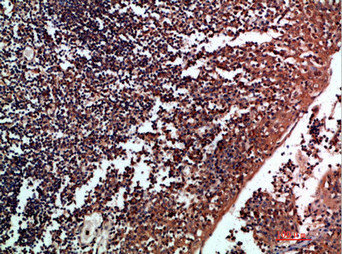

• Immunohistochemical analysis of paraffin-embedded human-tonsil, antibody was diluted at 1:200